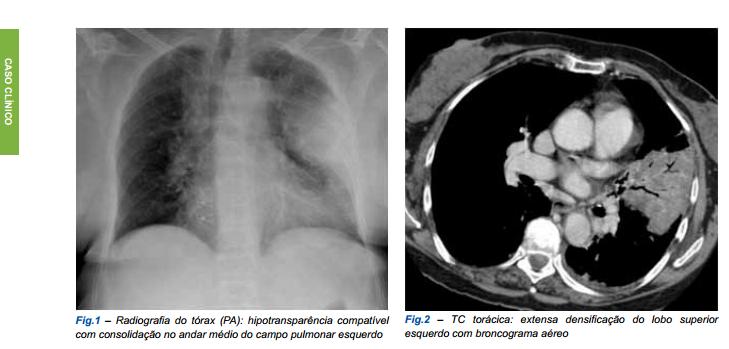

“Necrotizing pneumonia is a rare complication of community-acquired pneumonia associated with destruction of the lung tissue during the infectio...